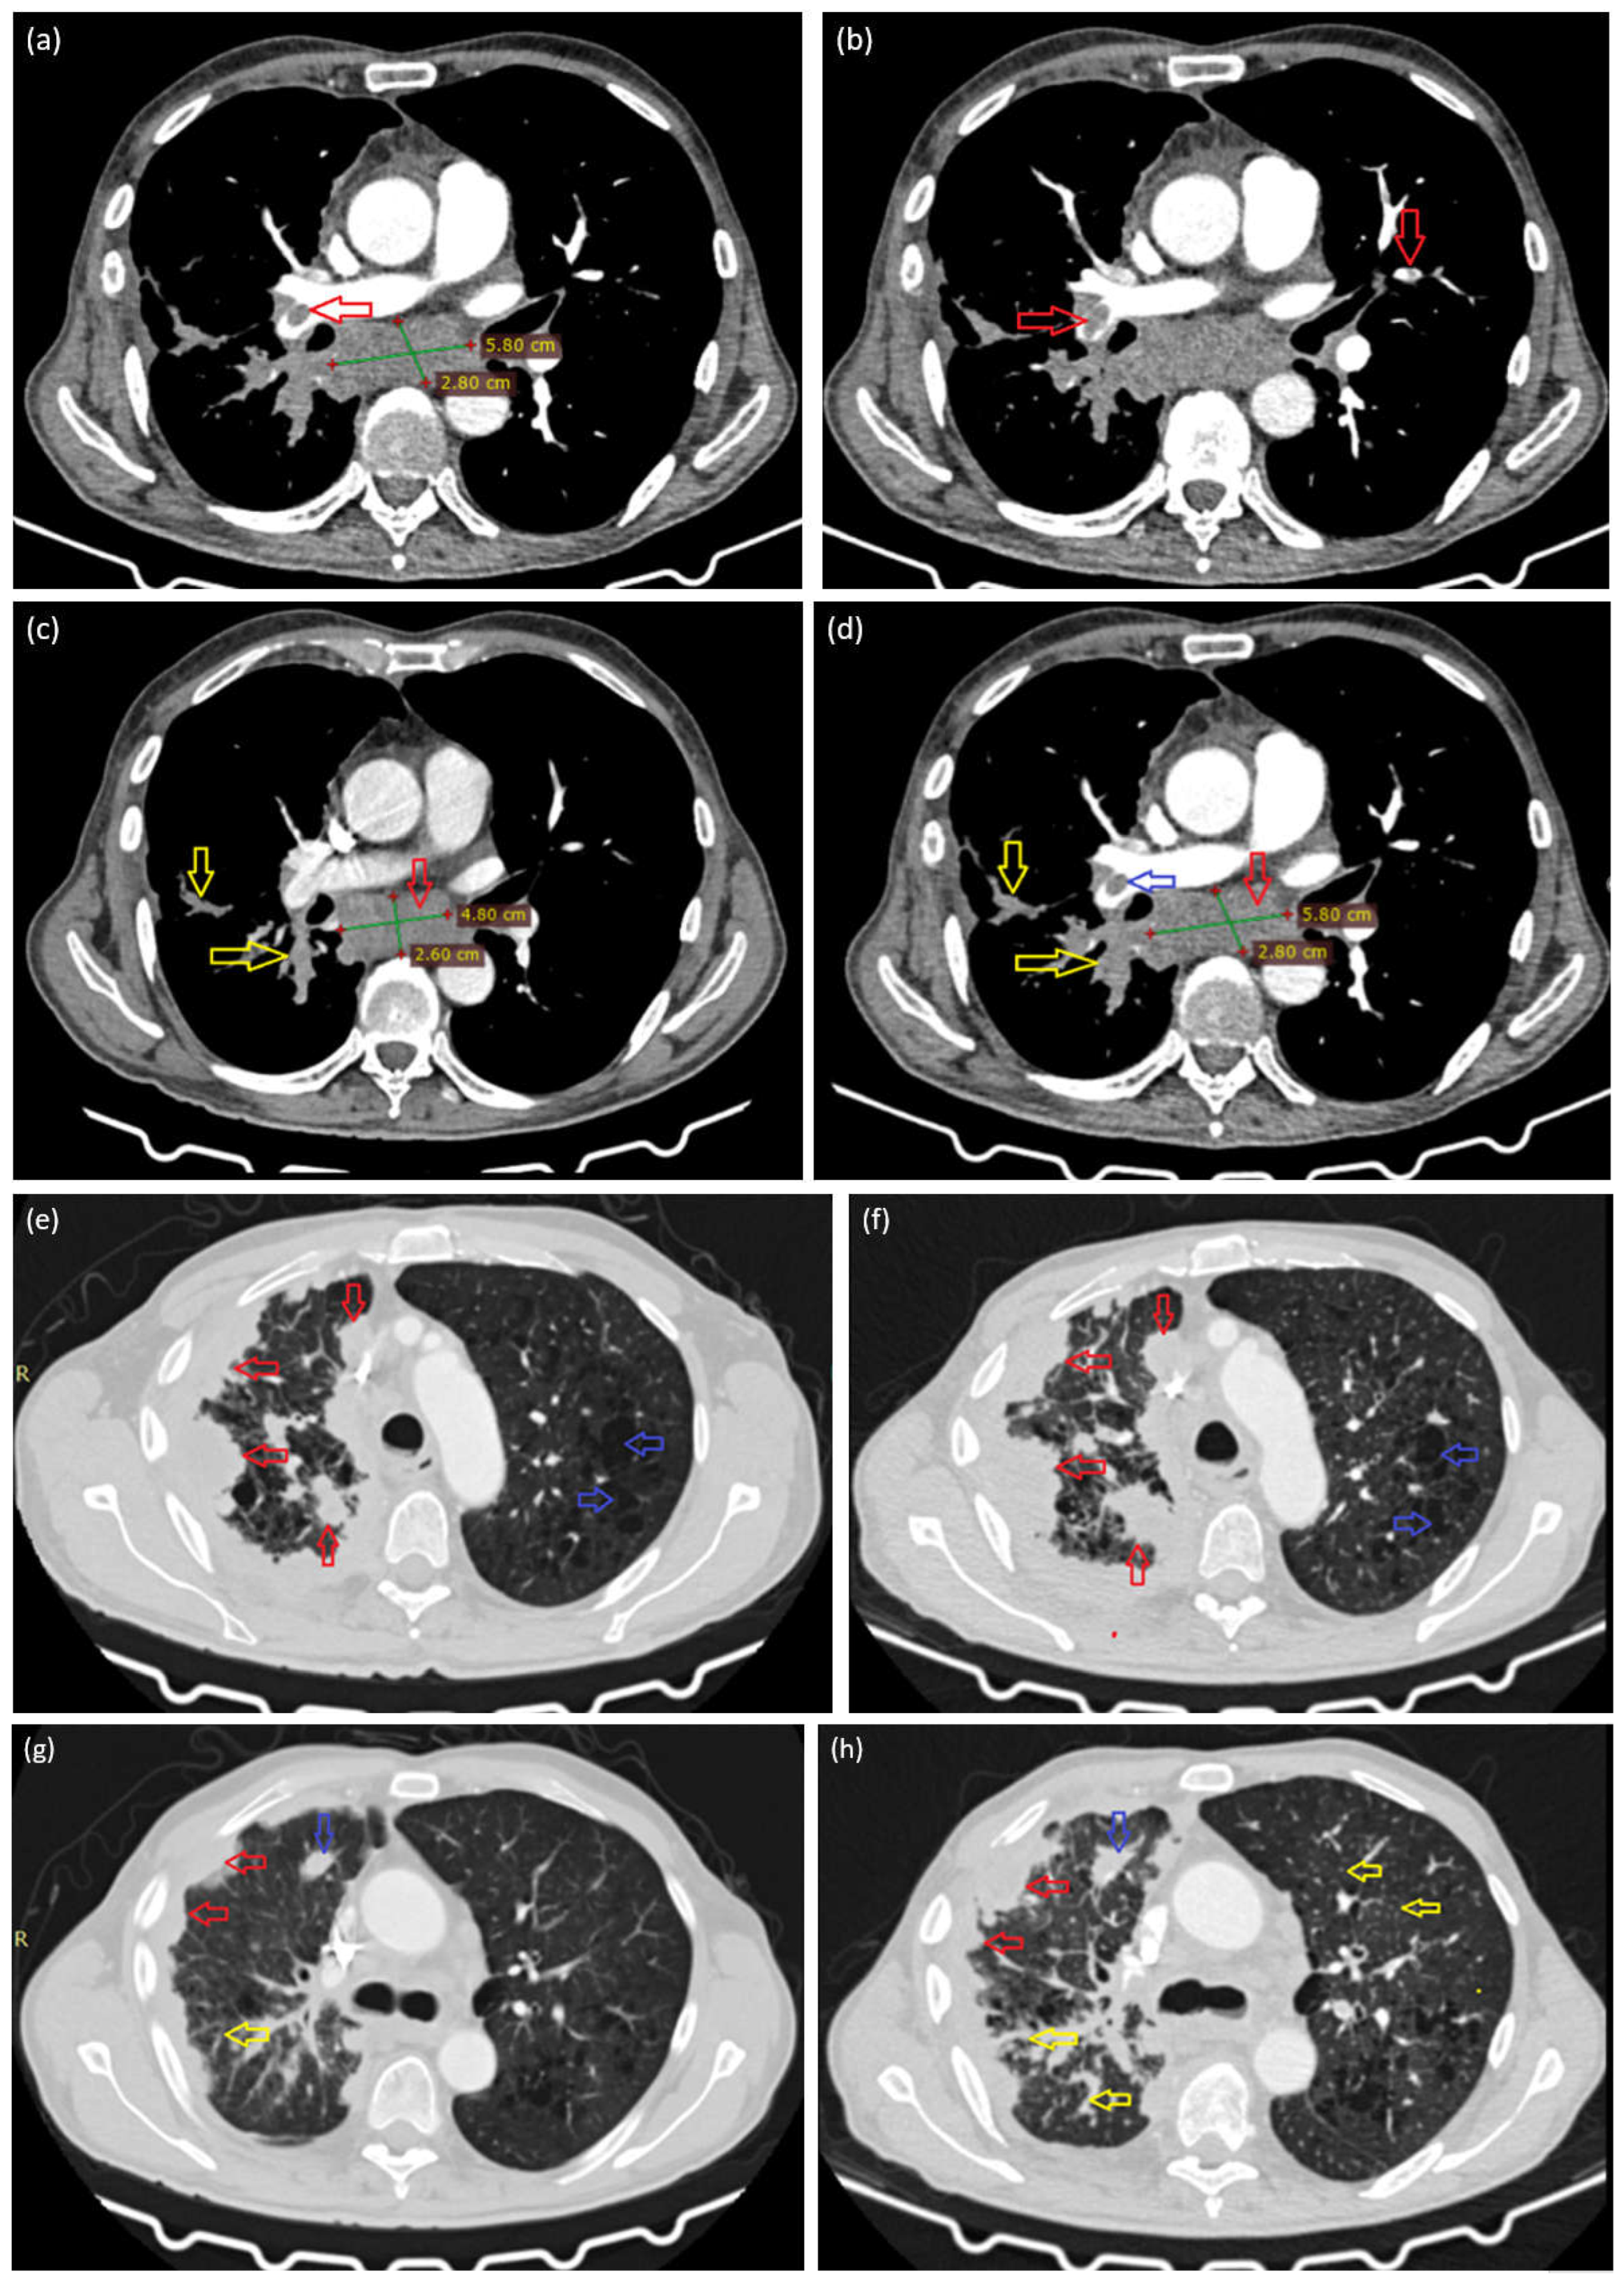

In addition, the patient has seropositive RA, managed with methotrexate, and valvular heart disease characterized by mild mitral and tricuspid regurgitation. In the context of the known rheumatologic disease, a contrast-enhanced chest CT scan was performed in February 2025, revealing a polymorphic lesion pattern, including a pseudonodular thickening of the right pleuro-parietal region (Figure 1a—red arrow), suggesting the possibility of mesothelioma, as well as other nodular pulmonary lesions, more prominently visible in the upper lobe of the right lung (Figure 1a—blue arrow). Additionally, discrete interstitial changes through interstitial thickening (Figure 1a—yellow arrow) and carinal adenopathy were identified, measuring 48 × 26 mm (Figure 1b—red arrow), along with panlobular emphysematous changes and perihilar cylindrical bronchiectasis. Previous investigations conducted in local healthcare facilities failed to determine the underlying etiology of these radiological findings.

The current CT examination, correlated with the previous investigation from another medical facility, reveals significant bilateral pulmonary arterial filling defects, both subocclusive and occlusive, predominantly on the right side (Figure 3a—red arrows; Figure 3b—red arrows, Figure 3d—blue arrows). In addition to the bilateral pulmonary thromboembolism, the investigation also indicates a progression of the lesions previously identified on the CT scan performed one month earlier, as evidenced by an increase in the size of the infracarinal lymphadenopathy from 48 × 26 mm to approximately 58 × 28 mm (Figure 3c,d—red arrows). Persistent iodophilic polynodular and lamellar pleural thickenings are also noted on the right side, extending along the peribronchovascular structures from the hilar region (Figure 3c,d—yellow arrows, Figure 3e,f—red arrows). Furthermore, the lung parenchyma demonstrates an emphysematous appearance (Figure 3e,f—blue arrows), with the presence of pulmonary micronodules and interstitial thickening (Figure 3g,h—yellow arrows).

Figure 1. Right pleural thickening with an irregular, pseudonodular appearance and a small right apical pulmonary nodule (a); infracarinal adenopathic mass measuring 48 × 26 mm (b).

Figure 3. Central embolus in the right pulmonary artery, and infracarinal lymph node (a). Bilateral pulmonary arterial filling defects, both central and peripheral and subocclusive and occlusive in nature (b). Comparative imaging assessment between the lesions documented one month prior to admission ((c,e,g)—left-sided images) and those identified during the current evaluation at our clinic ((d,f,h)—right-sided images).